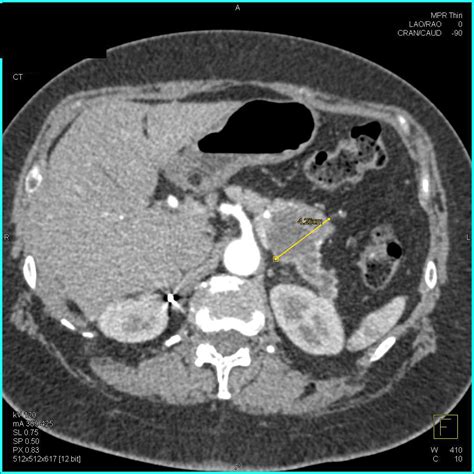

• Imaging Tests: Such as ultrasound, CT scan, or MRI to visualize the pancreas and its ducts.

These diagnostic tools help healthcare providers determine the cause of the enlarged pancreatic duct and develop an appropriate treatment plan.